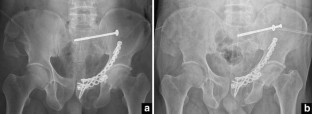

Fig. 1